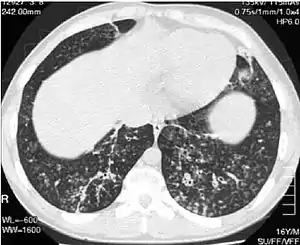

High-resolution computed tomography images of the lower chest in a 16-year-old boy with diffuse panbronchiolitis | |

- High-resolution computed tomography scan of the thorax

- High resolution computed tomography (HRCT) images of the lower chest in a 16-year-old boy initially diagnosed with DPB (left), and 8 weeks later (right) after a 6-week course of treatment with erythromycin. The bilateral bronchiectasis and prominent centri-lobular nodules with a "tree-in-bud" pattern shows noticeable improvement.

The diagnosis of DPB requires analysis of the lungs and bronchiolar tissues, which can require a lung biopsy, or the more preferred high resolution computed tomography (HRCT) scan of the lungs.[7] The diagnostic criteria include severe inflammation in all layers of the respiratory bronchioles and lung tissue lesions that appear as nodules within the terminal and respiratory bronchioles in both lungs.[4] The nodules in DPB appear as opaque lumps when viewed on X-rays of the lung, and can cause airway obstruction, which is evaluated by a pulmonary function test, or PFT.[6] Lung X-rays can also reveal dilation of the bronchiolar passages, another sign of DPB. HRCT scans often show blockages of some bronchiolar passages with mucus, which is referred to as the "tree-in-bud" pattern.[7] Hypoxemia, another sign of breathing difficulty, is revealed by measuring the oxygen and carbon dioxide content of the blood, using a blood test called arterial blood gas. Other findings observed with DPB include the proliferation of lymphocytes (white blood cells that fight infection), neutrophils, and foamy histiocytes (tissue macrophages) in the lung lining. Bacteria such as H. influenzae and P. aeruginosa are also detectable, with the latter becoming more prominent as the disease progresses.[4][5] The white blood, bacterial and other cellular content of the blood can be measured by taking a complete blood count (CBC). Elevated levels of IgG and IgA (classes of immunoglobulins) may be seen, as well as the presence of rheumatoid factor (an indicator of autoimmunity). Hemagglutination, a clumping of red blood cells in response to the presence of antibodies in the blood, may also occur. Neutrophils, beta-defensins, leukotrienes, and chemokines can also be detected in bronchoalveolar lavage fluid injected then removed from the bronchiolar airways of individuals with DPB, for evaluation.[4][9]